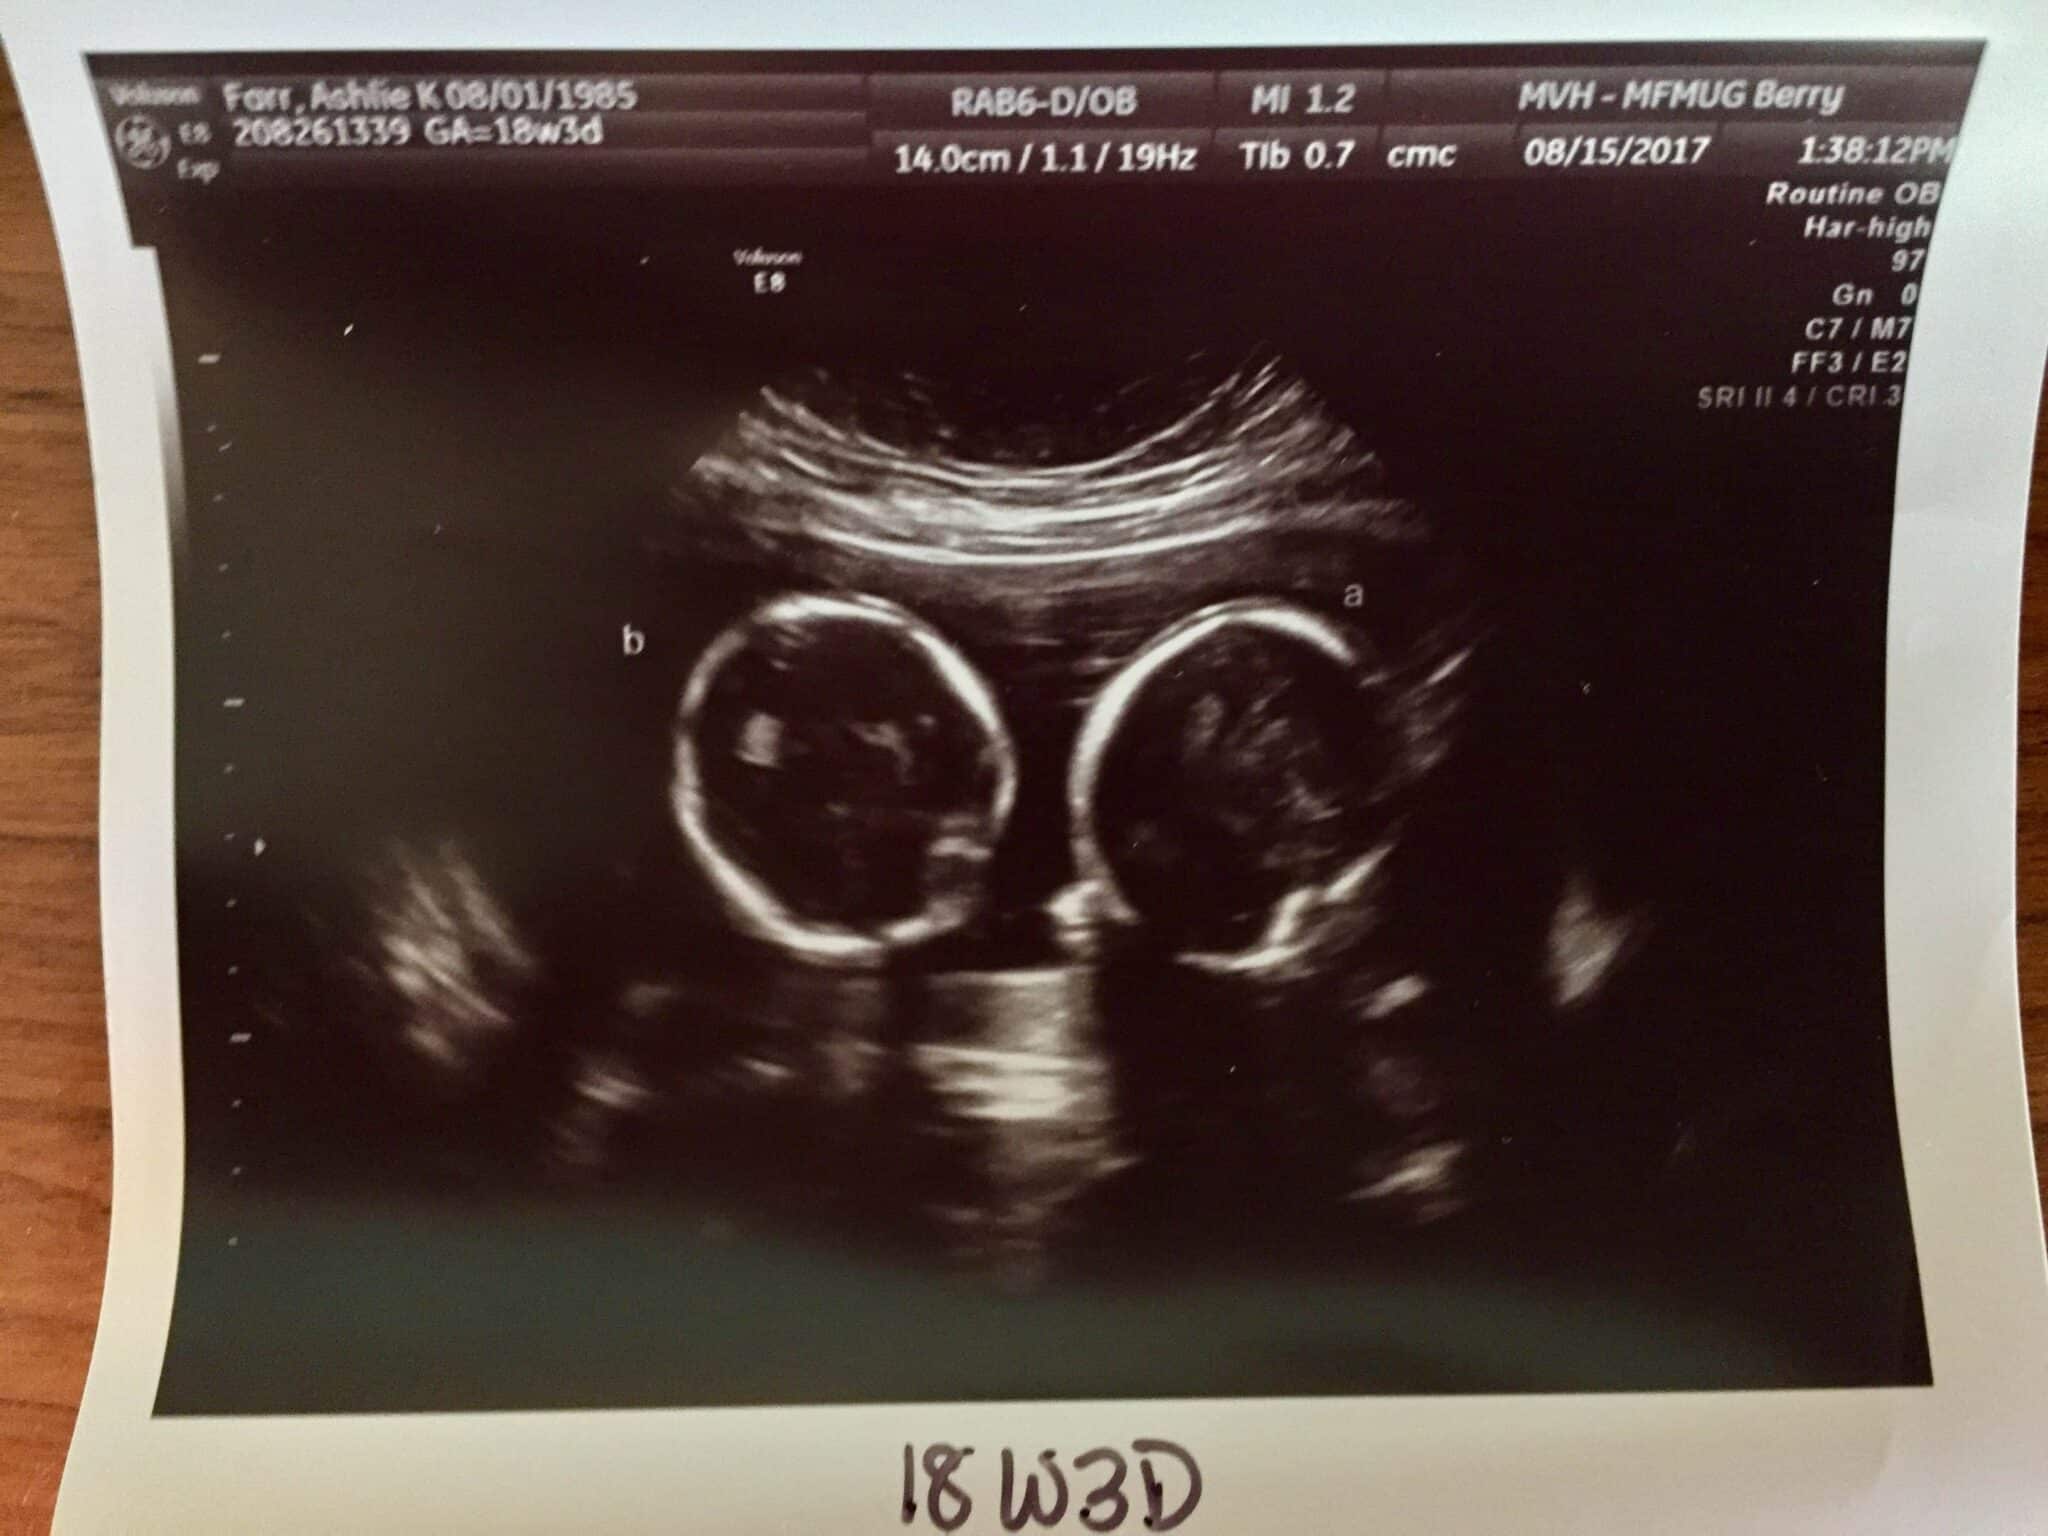

Ultrasound Photos at 18 Weeks Pregnant With Twins

Between weeks 18-22 you’ll have a level 2 anatomy scan. This is when you can typically find out the sex(es) of your babies. Don’t be surprised, however, if it’s too difficult to see one or both babies’ genitalia to determine the sex, most often because of the position the babies are in. During this scan, your medical team will be assessing the development of each baby’s brain, face, heart, spine, and other major organs, as well as the placement of the placenta(s), umbilical cords, and amniotic fluid levels. Do not be surprised if you are asked to come back for a follow-up scan. This is very common with multiple birth pregnancies because it’s often difficult for the technician to get a good picture if your babies are not cooperating.